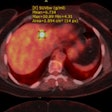

Avicenna.AI launches pulmonary embolism program